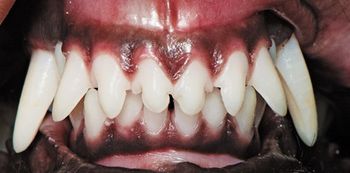

When hair becomes embedded in the oral cavities of your veterinary patients, it can cause inflammation and the destruction of periodontal attachment. Know where to look for it, how to treat it and how to keep it from recurring.